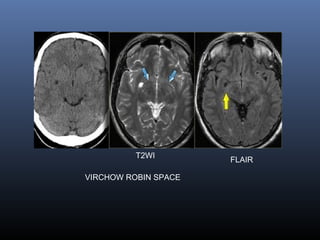

LACUNAR INFARCT

 Lacunar infarcts are small infarcts(less than 15mm)

in the deeper parts of the brain (basal ganglia,

thalamus, white matter) and in the brain stem.

Lacunar infarcts are caused by occlusion of a single

deep penetrating artery.

Lacunar infarcts account for 25% of all ischemic

strokes.

Atherosclerosis is the most common cause of

lacunar infarcts followed by emboli.

25% of patients with clinical and radiologically

defined lacunes had a potential cardiac cause for

their strokes.

 DD WITH VIRCHOW ROBIN SPACES

VIRCHOW ROBIN SPACE

FLAIR

T2WI